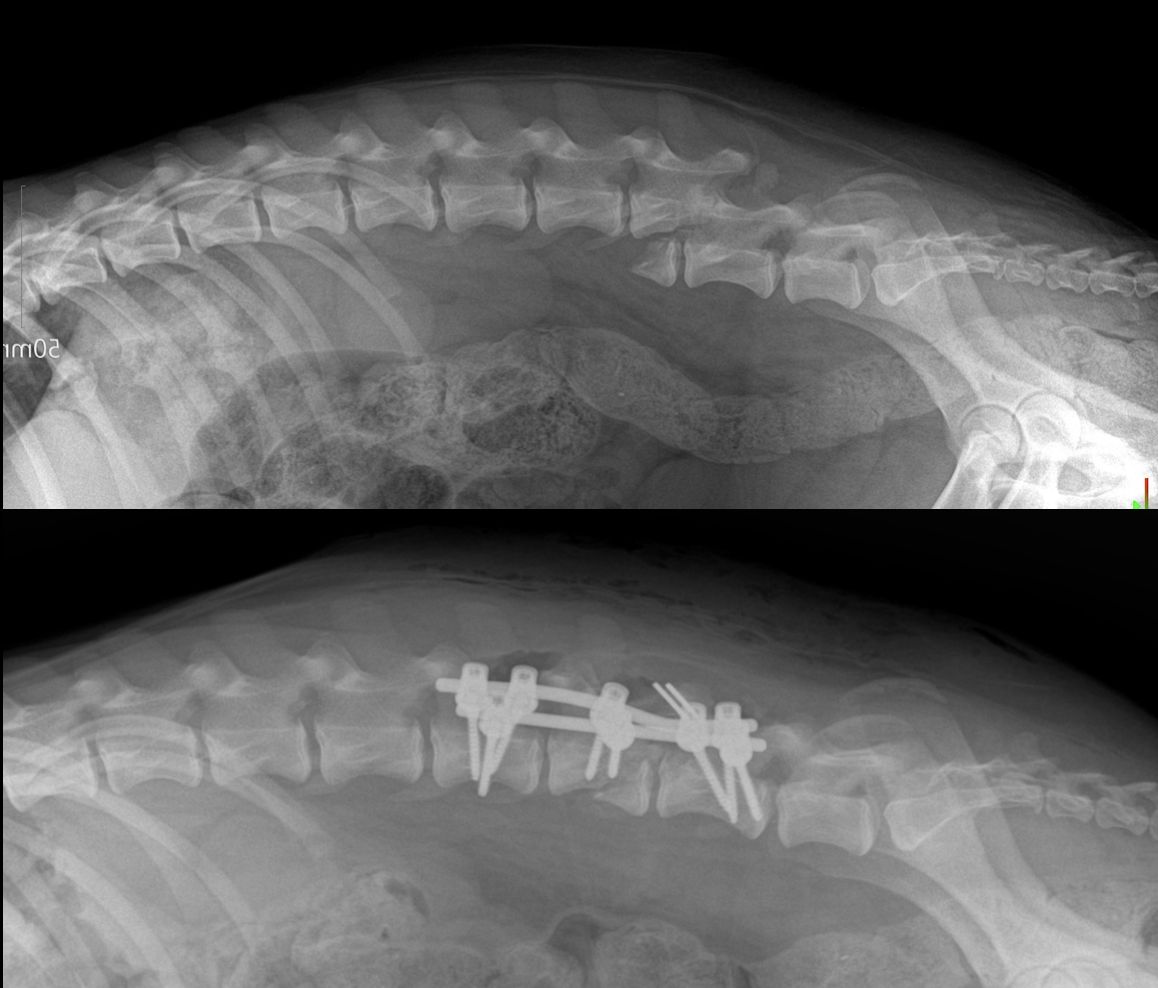

Glücklicherweise überlebte Merry die Nacht, jedoch zeigte das Röntgenbild eine schwere Verletzung der Wirbelsäule. Wir nahmen Kontakt mit Dr. Hristov von der Klinik Elpida in Varna für eine Konsultation auf und brachten Mary am 28. nach Varna zur Untersuchung. Am 29. fand die Operation statt, die sehr gut verlaufen ist.

Nach den heutigen Informationen frisst Merry gut und ist sehr fröhlich. Sie hat sogar schon einige kleine „Unfug“-Momente gehabt, da sie am liebsten schon wieder laufen und rennen möchte. Leider hat sich ihr neurologischer Zustand bisher nicht verändert – sie kann ihre Hinterbeine weiterhin nicht bewegen.